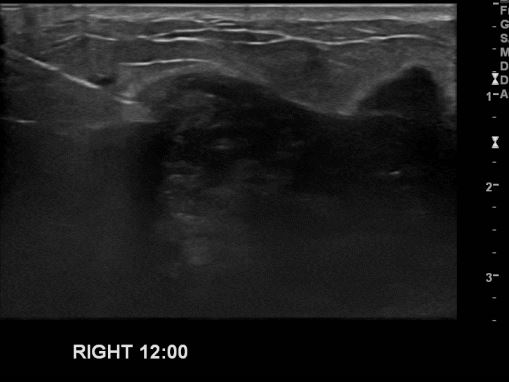

상기환자 유방에 만져지는 멍울로 내원하신 50대 여성분으로 우측 12시 방향에 만져지는 멍울 조직검사 시행하여 우측 침윤성 유관암 진단 되었습니다.